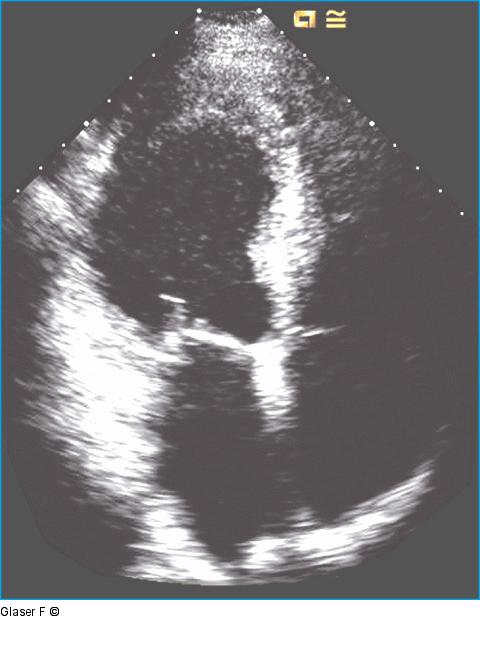

Abbildung 2: Lange Achse Apikale Lange Achse: Global mäßig reduzierte Linksventrikelfunktion, vergrößerter linker Vorhof, posterolaterale Hypo- bis Akinesie. |

Apikale Lange Achse: Global mäßig reduzierte Linksventrikelfunktion, vergrößerter linker Vorhof, posterolaterale Hypo- bis Akinesie. |